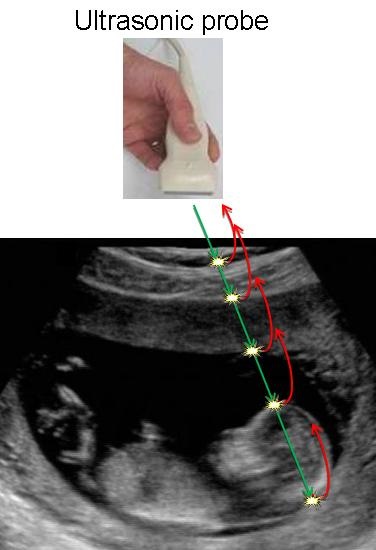

Ultrasound Imaging Application

An interesting application of our scheme is ultrasound imaging, in which the signal received from the tissue under test comprises a stream of short Gaussian pulses. Applying our scheme on data recorded with GE Healthcare's Vivid-i system, we reconstructed the original signal as depicted in the figure below. The reconstruction is based on 17 samples only, whereas current ultrasonic imaging systems use for the same scenario 4000 samples, emphasizing the potential of our scheme in reducing sampling rate in such